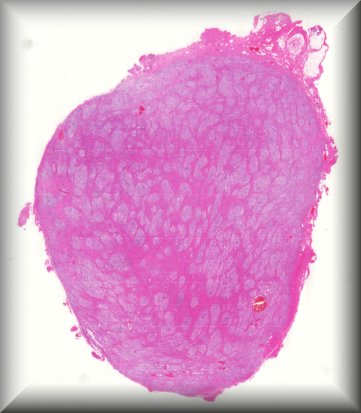

Alexandre Moulin (Laussane): Pigmented ciliary body mass in a 35 yo male. |